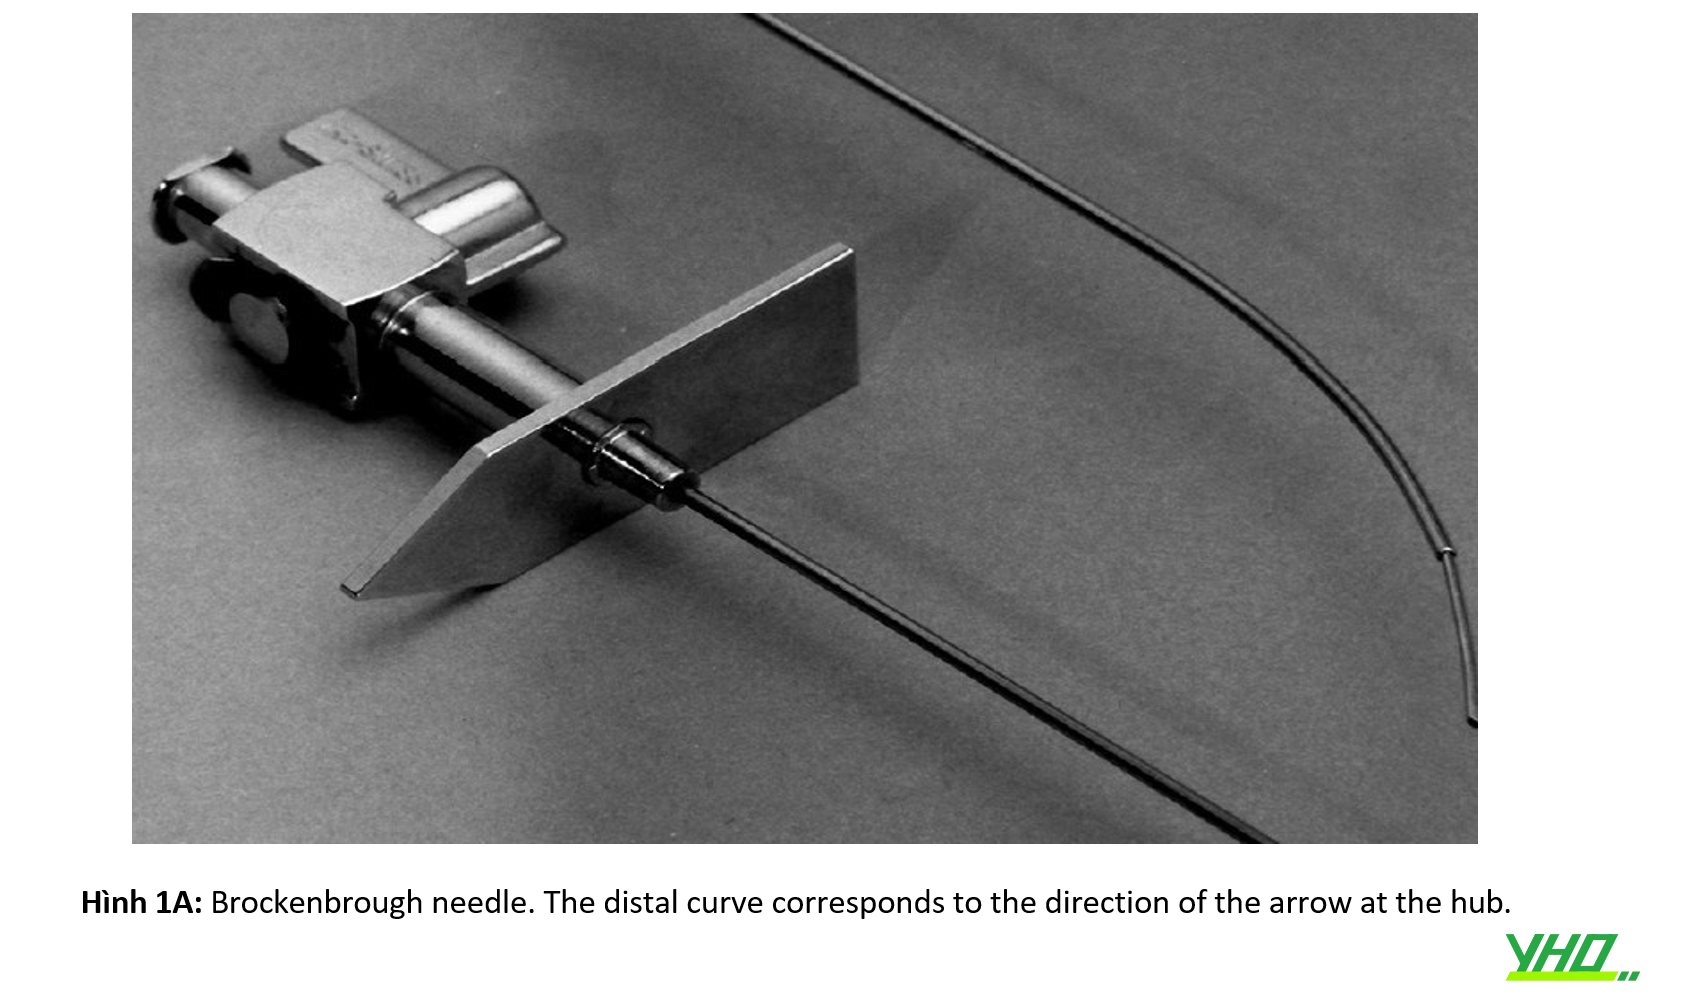

Kim Ross thưở ban đầu đã được cải tiến bởi Brockenbrough bằng cách giảm đường kính kim từ 18G -> 21G ( ở 1,5 cm đầu xa). Điều này mang lại sự an toàn cao hơn trong trường hợp kim đâm ra bên ngoài khoang nhĩ trái.

Kim Brockenbrough (Medtronic, Minneapolis, Minnesota) chỉ có một kích cỡ. (hình 1A)

Một số hãng sản xuất Kim xuyên vách với các độ cong khác nhau chẳng hạn như dòng BRK (St. Jude Medical, St Paul, Minnesota). (Hình 1B)

Khử trùng lại (hấp lại) không được khuyến nghị do lòng kim dài, khó vệ sinh.